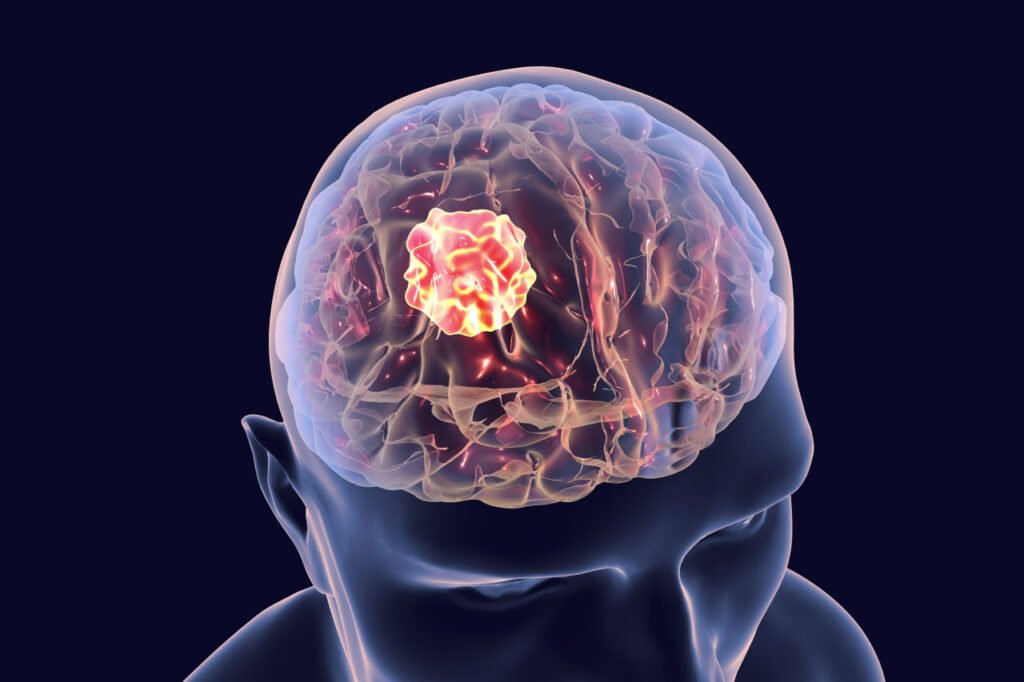

ابزار کوچکی به اندازه دانه برنج با قابلیت تست بیش از ۲۰ درمان به طور همزمان برای سرطان مغز

[ad_1] پژوهشگران یک ابزار بسیار کوچک توسعه دادهاند که میتواند بهترین روش درمانی را برای سرطان مغز شناسایی کند. به گزارش سرویس اخبار فناوری و تکنولوژی تکنا، دستگاه جدید پژوهشگران تنها به اندازه یک دانه برنج بوده و به طور همزمان قادر است ۲۰ نوع روش درمانی را برای تشخیص بهترین نوع درمان در سرطان مغز مانند گلیوما است کند. این ابزار در هنگام جراحی درون مغز قرار داده شده و سپس در یک محیط کوچکی از مغز آثار داروها را شناسایی کند. با رفع محدودیتهای مربوط به روشهای تست…